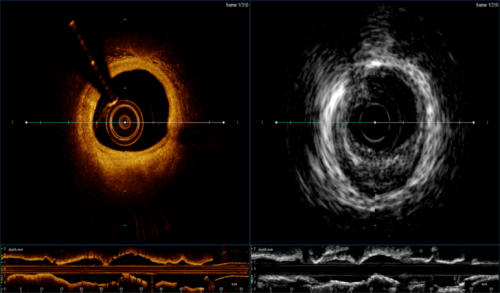

本次获得注册证的血管内成像设备及导管是由全景恒升(Panovision)和哈尔滨医科大学附属第二医院于波教授团队共同研发,这是一款将现有IVUS,OCT两项技术融合的新一代腔内影像机器及导管,产品拥有智能的算法平台,突破性的探头融合技术和优异的图像质量,提供一系列多模态的成像方式和临床诊断影像学解决方案,旨在帮助术者全面准确获取管腔IVUS,OCT信息,助力术者实现精准医疗。

S1配备手动和自动测量管腔面积、直径、长度且提供智能支架和管腔辅助探测功能,辅助分析支架贴壁不良,专业直观的软件界面设计,实现各种功能一键切换,尽享丝滑;配备三种类型的成像模式,医师可选择IVUS,OCT双模水平视图或重叠融合视图,也可选择单模成像,此外血管三维重建体渲染技术提供了360度全方位观察视角并且可多角度旋转拉伸,让临床医师从多维度观察病变。

作为冠状动脉介入诊疗中最主要的两种血管腔内影像学技术,两种影像学技术已成为心血管介入医生不可或缺的辅助手段,其自身都有一定的优势和缺陷,OCT具有更高的分辨率,能更好地分析斑块成分,但是穿透深度有限;IVUS具有更强的穿透力,能够更深层的成像,但空间分辨率较弱。

也正是因为如此,将二者合一才能帮助医师全面准确获取管腔信息,精准实现高质量PCI。